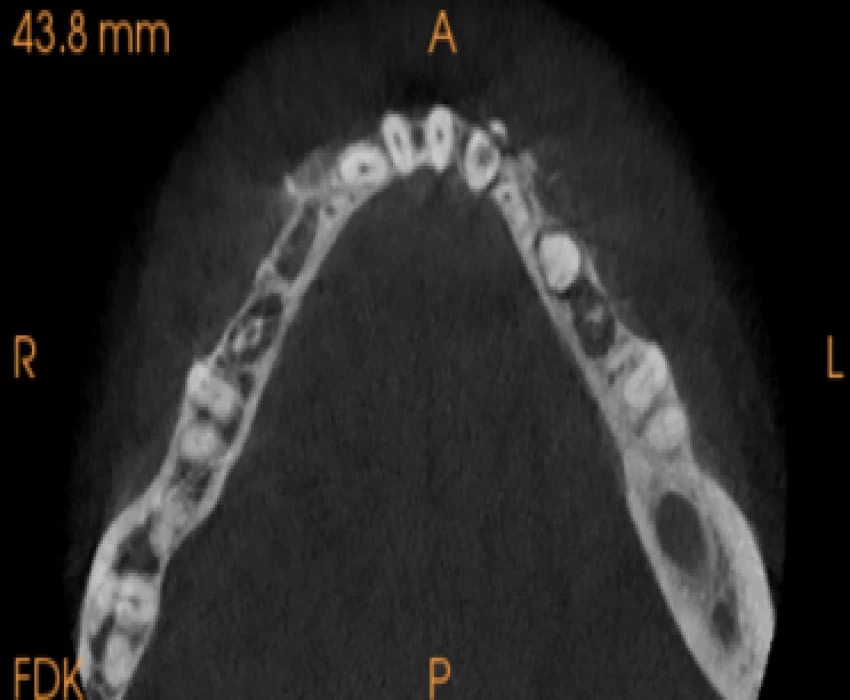

On intra-oral examination generalized loss of cervico-occlusion height and colour of the teeth appeared opalescent and brown in colour.

On the basis of history, clinical examination, and radiographic investigation final diagnosis was given as Amelogenesis imperfecta- Hypoplastic Type.

In patients with hypoplastic amelogenesis imperfecta, the basic alteration centers on inadequate deposition of enamel matrix. In the generalized pattern, pinpoint-to-pinhead–sized pits are scattered across the surface of the teeth and do not correlate with a pattern of environmental damage. The buccal surfaces of the teeth are affected more severely. Both dentitions, or only the primary teeth, may be affected. All of the teeth may be altered, or only scattered teeth may be affected.